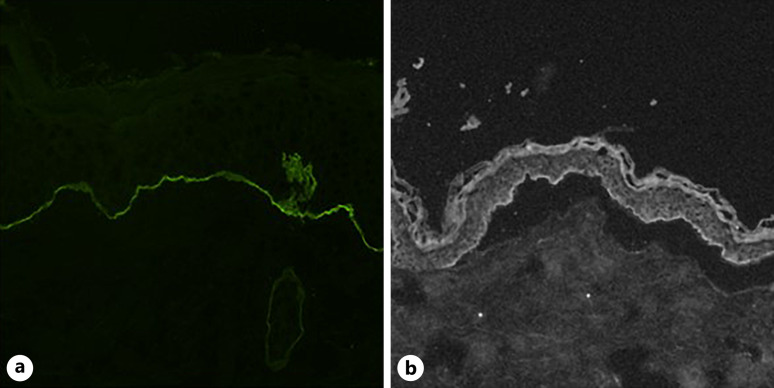

Case presentation: We present a case of a full-term female infant with severe cutaneous and respiratory symptoms due to NLABD. Diagnosis was confirmed by immunofluorescence on the infant's skin biopsy, while IgAs directed against the basement membrane of the skin and mucosa were identified in the mother's milk. The infant fully recovered after nearly 8 weeks of intensive multidisciplinary care, including non-invasive ventilation, nutritional support, wound care, systemic corticoid treatment, and breastfeeding discontinuation.